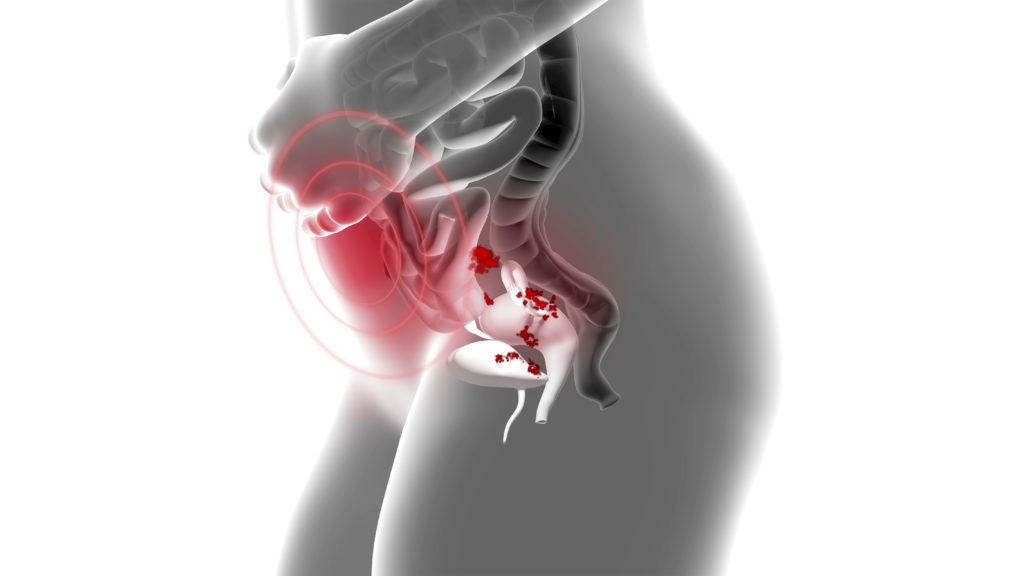

L’ENDOMETRIOSE, C’EST QUOI ?

D’après l’association EndoFrance : « L’endométriose, se définie comme la présence en dehors de la cavité utérine de tissu semblable à la muqueuse utérine qui subira, lors de chacun des cycles menstruels ultérieurs, l’influence des modifications hormonales. ».*

Ce qui signifie que lors des règles, la muqueuse de l’utérus se détache et s’évacue naturellement par le vagin. Dans le cadre de l’endométriose, le reste de la muqueuse s’écoule aussi dans le reste du corps et forme des adhérences qui créent des douleurs et qui peuvent être très invalidantes.

On dit souvent que c’est la maladie des règles, mais pas seulement c’est une maladie qui intervient tout au long du cycle et peut parfois attaquer des organes.

La première est l’endométriose superficielle, autrement appelée péritonéale, elle désigne la présence de tissus d’endométriose au niveau du péritoine.

La deuxième est l’endométriose ovarienne. Cela signifie qu’il y a la présence d’un kyste endométriosique au niveau de l’ovaire.

La dernière est l’endométriose pelvienne profonde, également appelée . Elle désigne les lésions profondes situées sous la surface du péritoine. Ce type d’endométriose touche très souvent les ligaments utérosacrés, le cul-de-sac vaginal postérieur, l’intestin, le rectum, la vessie, les uretères mais également parfois le sigmoïde, le côlon droit, l’appendice et l’iléon.